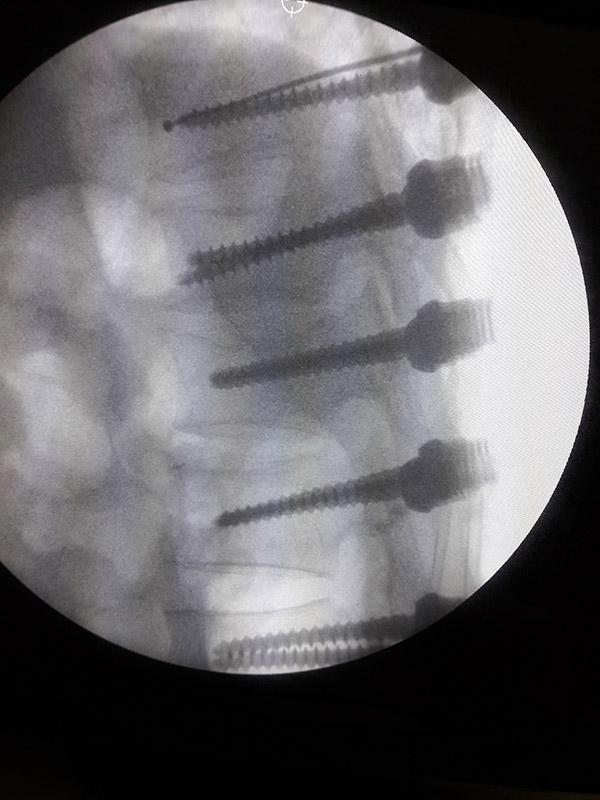

REBORN SPINAL STABILIZATION SYSTEM

Spinal Stabilization System Reborn ® Spinal Fixation System is an implant system used to treat a r...